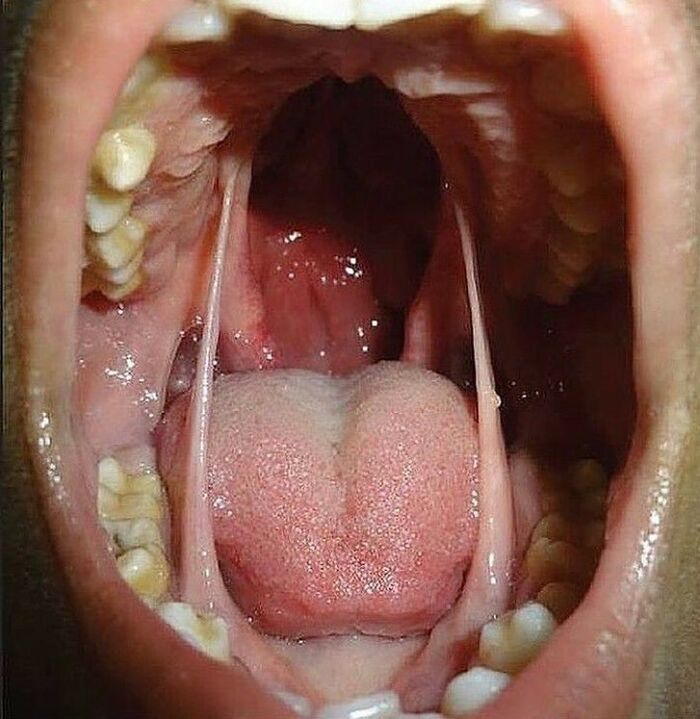

Ankyloglossia, also known as tongue-tie, is a congenital oral anomaly that may decrease the mobility of the tongue tip and is caused by an unusually short, thick lingual frenulum, a membrane connecting the underside of the tongue to the floor of the mouth. Ankyloglossia varies in degree of severity from mild cases characterized by mucous membrane bands to complete ankyloglossia whereby the tongue is tethered to the floor of the mouth.

My son was tongue tied. He had it "clipped" when he was around 4. The improvement in speech was instant.